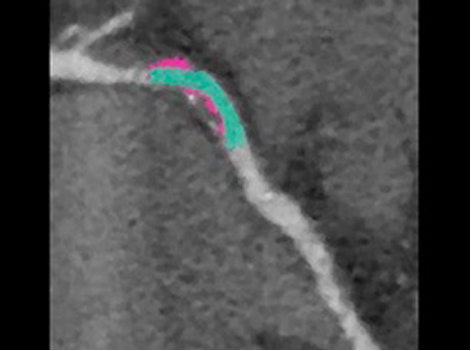

如果将导管消融作为一种治疗选择,术前规划可以包括使用 MR 或 CT 成像来确定手术的解剖目标和了解房颤的程度。这些图像可以帮助指导决策是否有必要对某些人群进行左心耳封堵。3

借助鲜血、3D 序列实现解剖结构和心脏血管的可视化。

了解更多信息